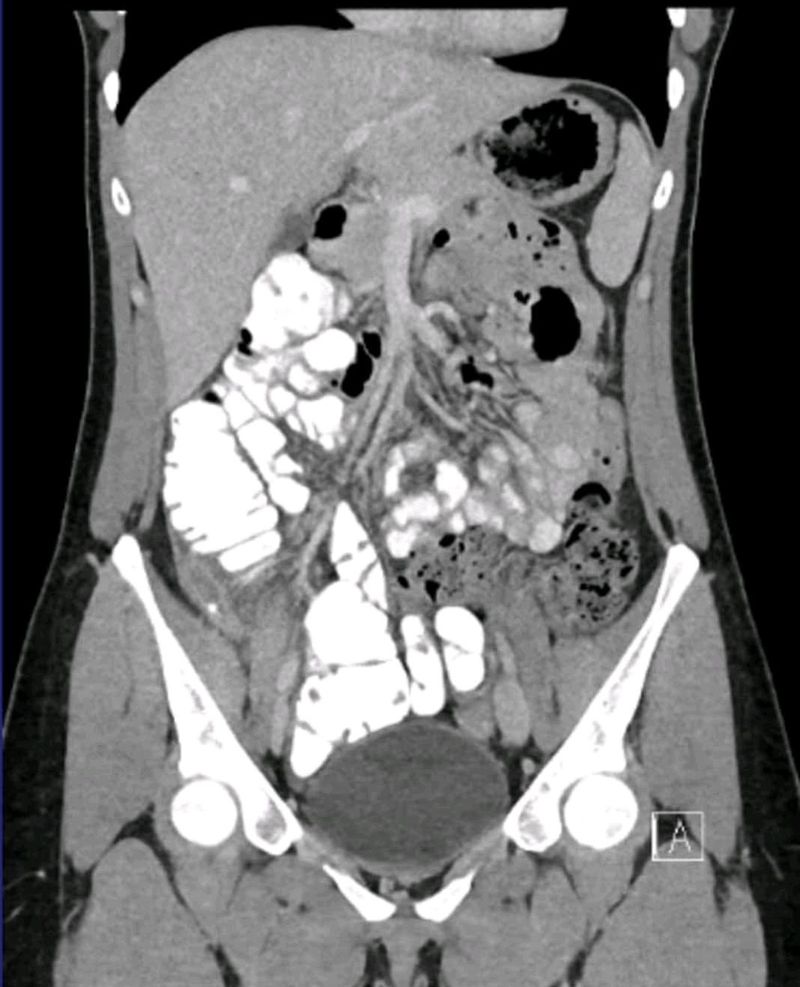

Distended small bowel, potential volvulus